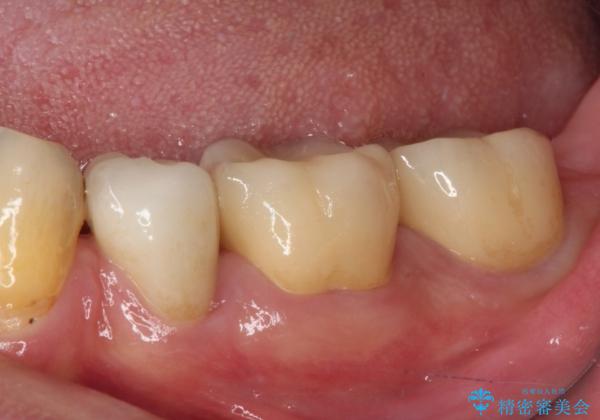

虫歯を取り除き、仮歯を装着した時点でしみる感覚は改善されました。

オールセラミッククラウン装着後も経過は良好です。